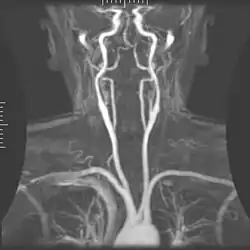

Magnetic Resonance Angiography

Magnetic Resonance Angiography -